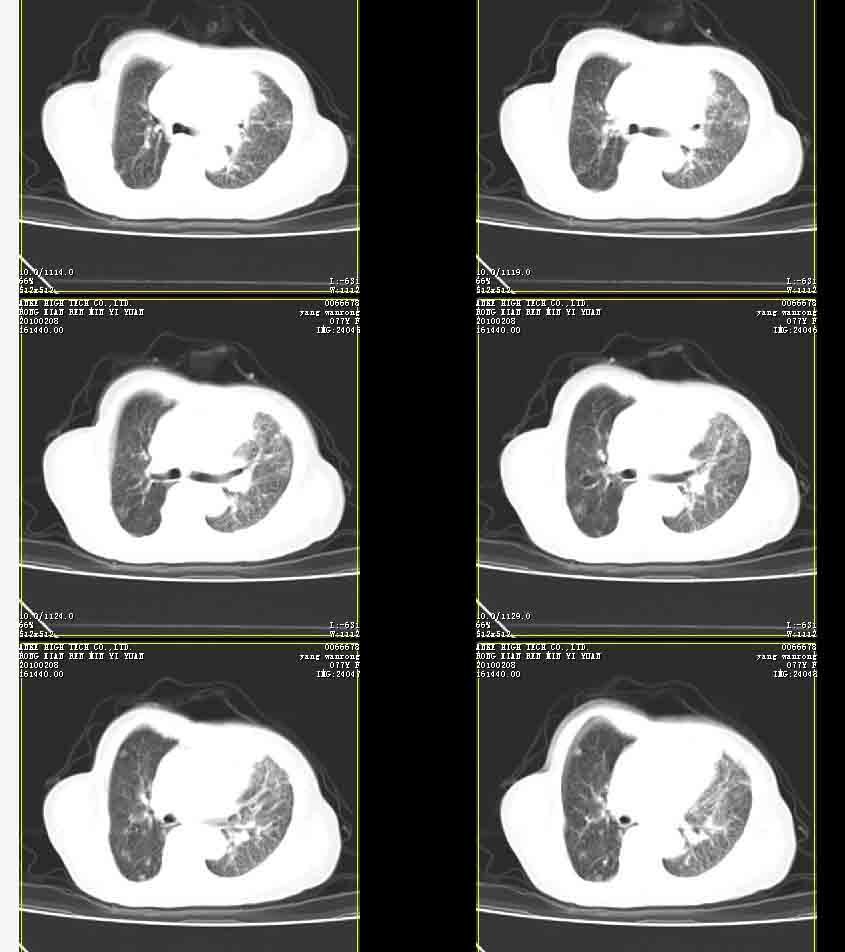

女77岁因左侧胸痛伴咳嗽入院;提示:病灶平扫45hu,强化145hu补充:双肺内未闻及干湿罗音

我的诊断意见:左肺上叶前段肺癌伴节段性不张。

在不张的肺内见到不规则的软组织,而且强化是不均匀的(该点可能是我的图像作得不好的原因)。

右肺近胸膜下区散在结节,性质?

请教左侧肺含气不良用什么解释更好?

左上肺前段可见分叶团块影,强化明显,周围见带状不张影,右肺结节,左肺沿肺纹模糊片状影,考虑左上肺占位,肺癌可能性大。

考虑左肺上叶前段肺癌伴节段性不张、肺内转移,建议薄层扫描。